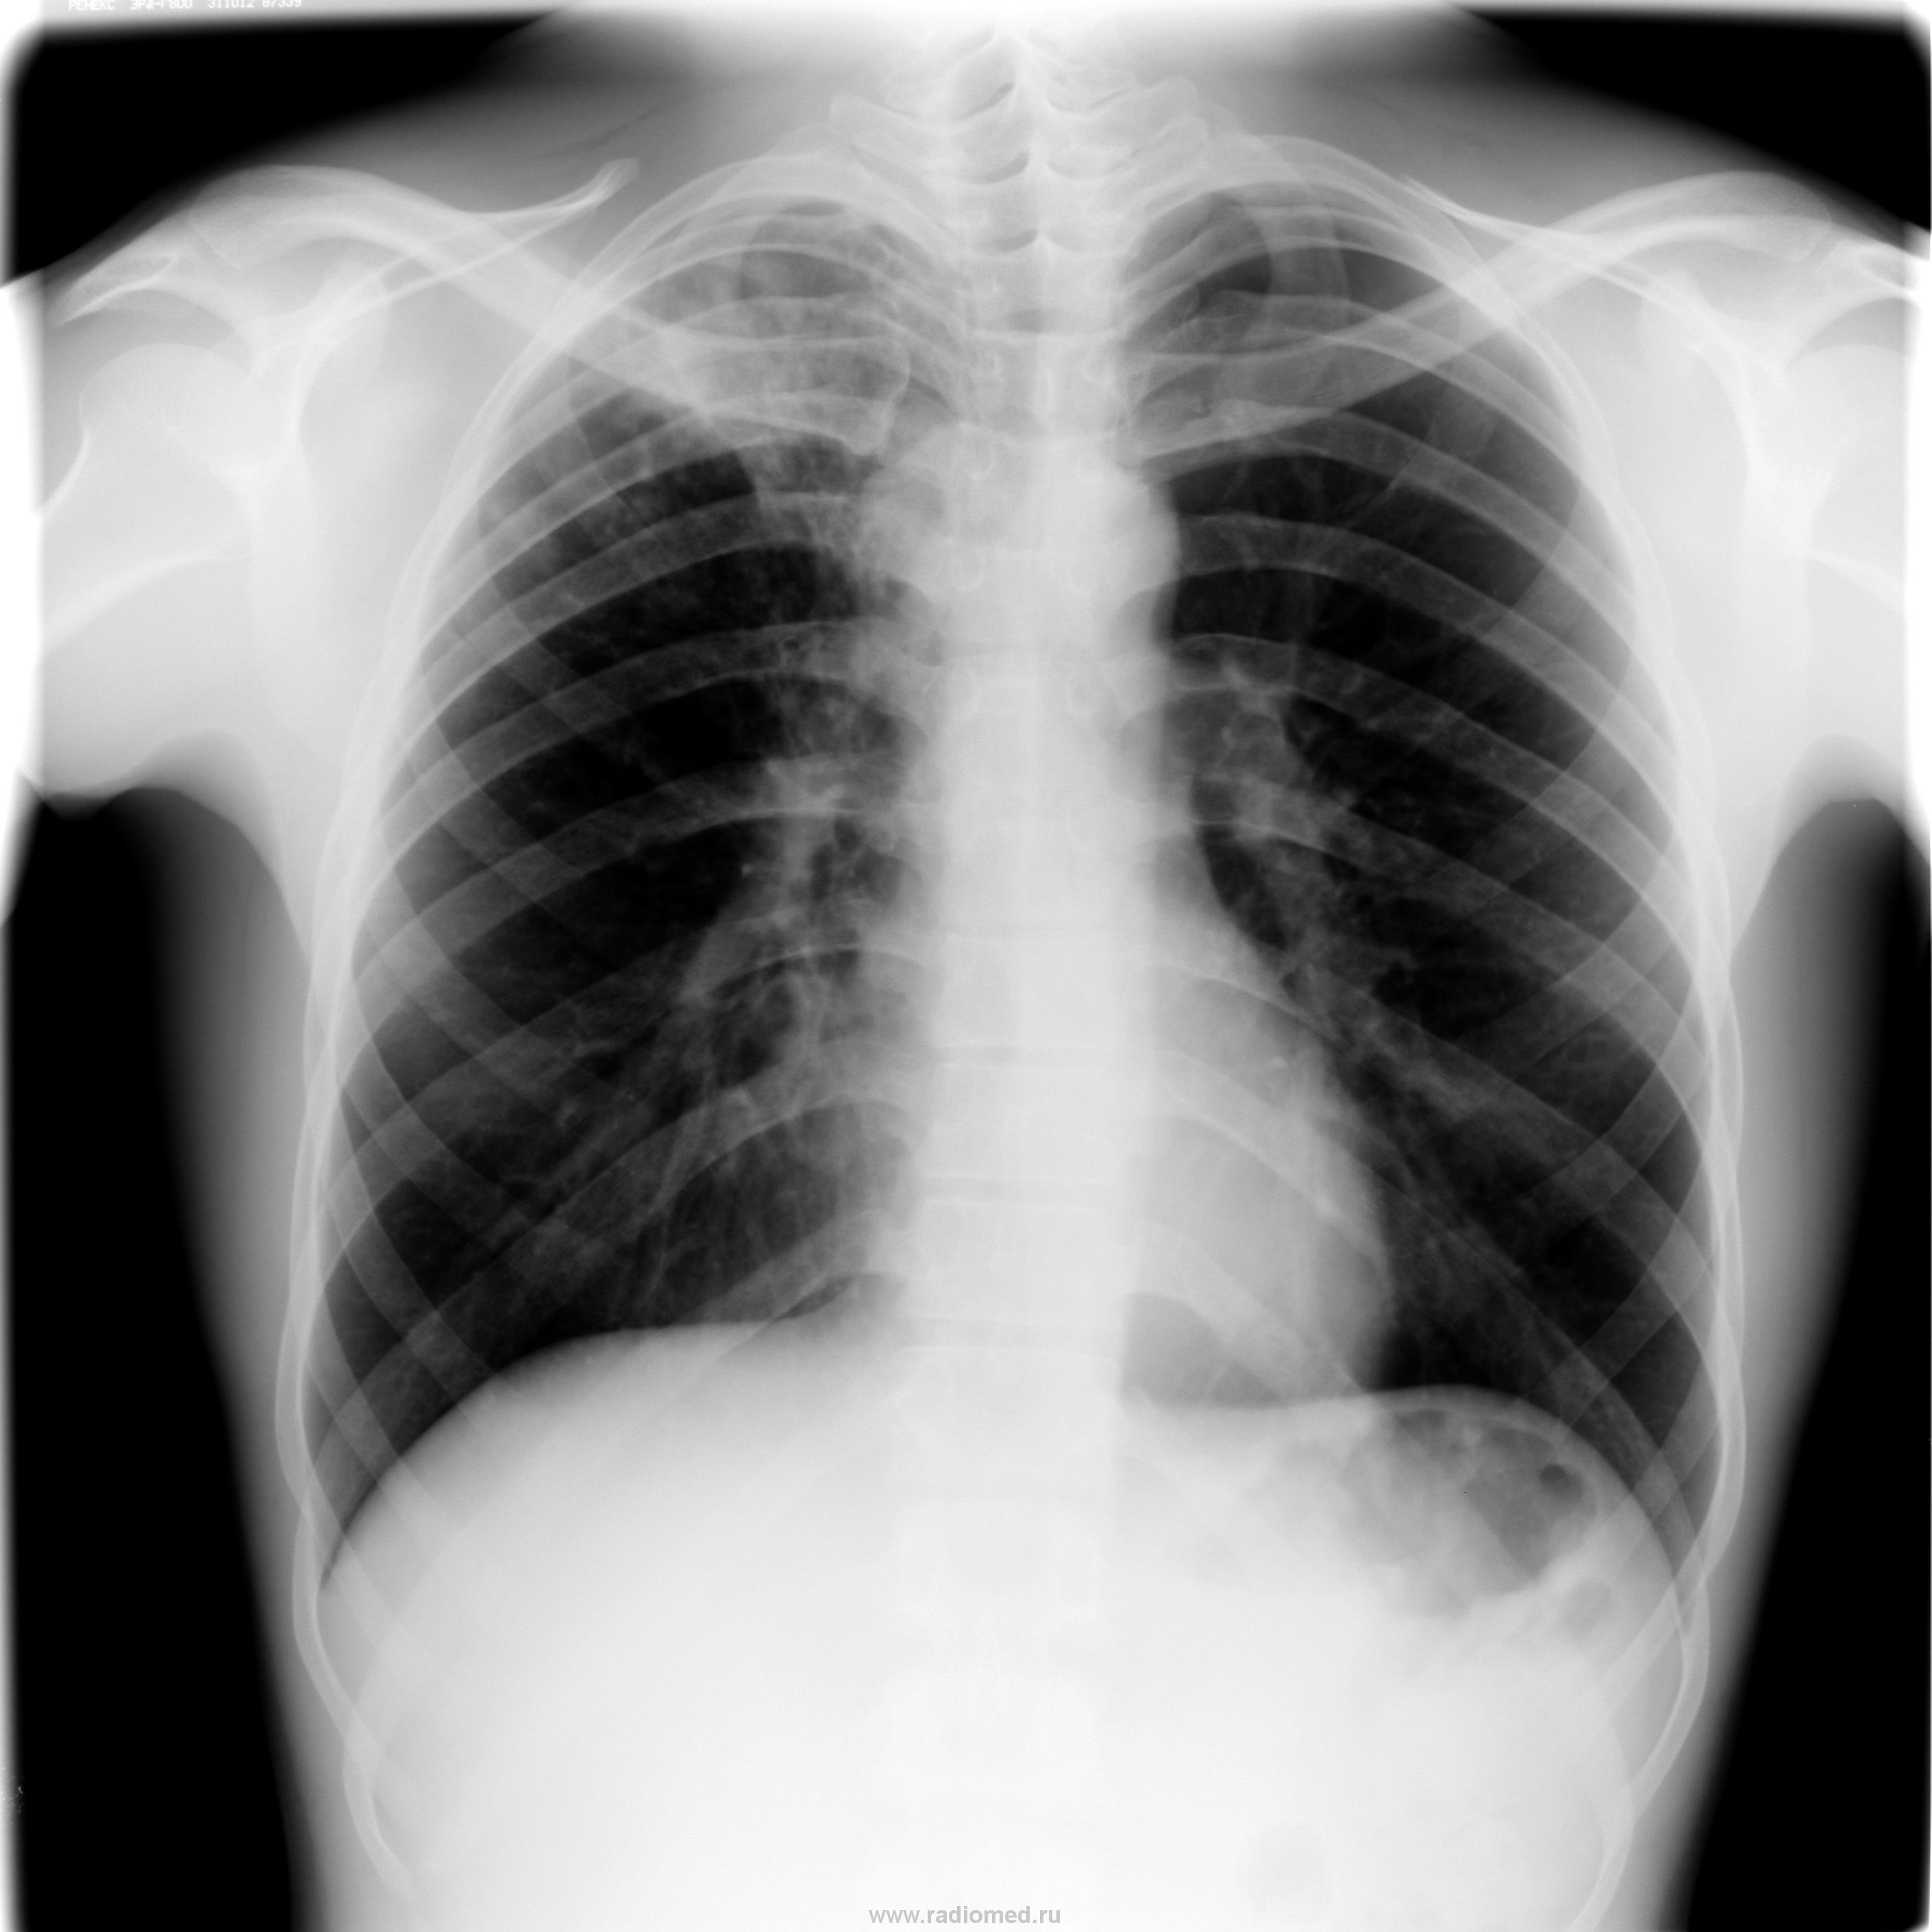

Мужчина 26 лет. Без жалоб.Думаю, двух мнений быть не может.

Неее..., пневмонией оказаться не сможет.Пациент ещё и из "очага смерти", как выражаются фтизиатры.В семье имеется умерший от туберкулёза.

Инфильтративный туберкулез S1,2 правого лёгкого в фазе распада и обсеменения

Cлучай рядовой для нас, уважаемая Сольвейг. Для пациента частной клиники очень не рядовой.За почти год моей работы там выявлено трое, все поехали лечиться в ЦНИИТ.Не любят они бесплатную районную медицину.В данном случае имеетя дополнение к анамнезу: какое-то время назад жена пациента скончалась "от иммунодефицита".Обследовался он сам, "на всякий случай".Архива не имею.